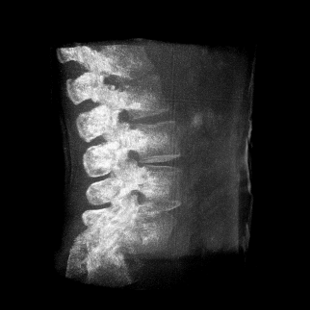

術(shù)中三維成像和橫斷面圖像提供多角度的手術(shù)診斷信息,輔助醫(yī)生進(jìn)行術(shù)中評(píng)估判斷,諸如骨折復(fù)位情況和內(nèi)植入螺釘?shù)某叽绾臀恢?,輔助手術(shù)更好地完成。

提供更大的術(shù)中三維成像視野,采集更多圖像信息,可一次拍全全段頸椎、全段腰椎、七節(jié)胸椎、雙側(cè)骶髂關(guān)節(jié)、股骨頭及單側(cè)盆骨。